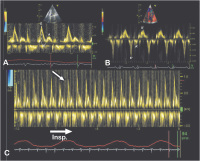

Abbildung 4: Typische Hinweise auf eine PC im transmitralen Doppler sowie im TDI. Aufgrund der hohen linksatrialen Füllungsdrücke findet sich eine hohe E-Welle, eine kurze Dezelerationszeit und eine kleine A-Welle (A). Im Unterschied zu einer restriktiven Kardiomyopathie sind die Geschwindigkeiten des Mitralanulus im TDI normal bis verstärkt (B) und es zeigen sich die charakteristischen Änderungen der Geschwindigkeiten im transmitralen Einstrom mit der Atmung (C). Unmittelbar nach Beginn der Inspiration (Pfeil) nimmt die maximale Geschwindigkeit um > 25 % ab. Zu beachten ist die langsame Durchlaufgeschwindigkeit (25 mm/s) bei der Aufzeichnung.